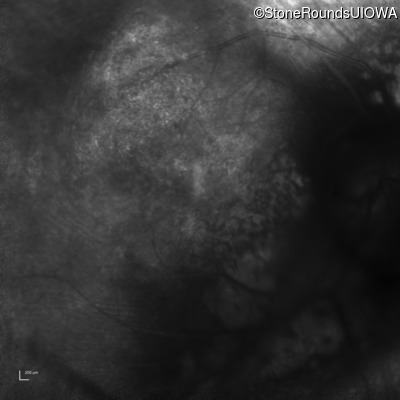

Infrared Fundus Photograph - Right - 20/150 sc

Exemplar

Infrared Fundus Photograph - Left - 20/100 sc